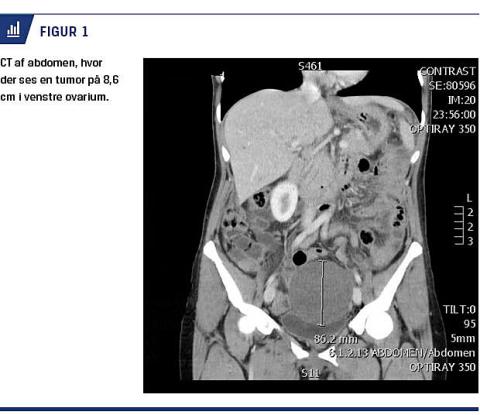

Ved den objektive undersøgelse fandt man abdomen med peritoneal reaktion og en udfyldning i venstre fossa. Ved indlæggelsen havde patienten en temperatur på 38 °C, koncentrationen af C-reaktivt protein var på 79 mg/l (normalværdi: < 8 mg/l) og koncentrationen af leukocytter på 12,2 × 109/l (normalområde: 3,5-10 × 109/l). En akut CT viste en 9 cm stor proces på venstre ovarium (Figur 1). Den blev radiologisk vurderet som en venstresidig ovariecyste med blødning og torsionssuspension. Man fandt en velplaceret spiral i uterus. Der var normale forhold i øvre abdomen, herunder pancreas.